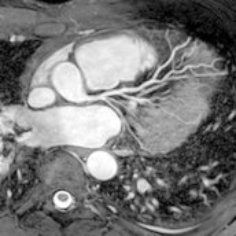

Der Schwerpunkt der MRT liegt in der Darstellung von Weichteilstrukturen, das heißt vor allem von nicht-knöchernen Strukturen. Die häufigsten Einsatzbereiche der Magnetresonanztomographie (MRT) sind die Diagnostik von Erkrankungen der Oberbauchorgane (Leber, Nieren, Nebennieren, Bauchspeicheldrüse), der Lymphknoten, der Gelenke und Muskeln, des Gehirns (inklusive der Gefäße), des Darms, des Herzens und der Gefäße oder auch der Brustdrüse (Mamma). Insbesondere lassen sich Entzündungen oder gut- bzw. bösartige Tumoren hervorragend darstellen. Da die Lunge vorwiegend Luft beinhaltet und die Luft kein Signal im MRT gibt, eignet sich hierfür das CT deutlich besser zur Darstellung.